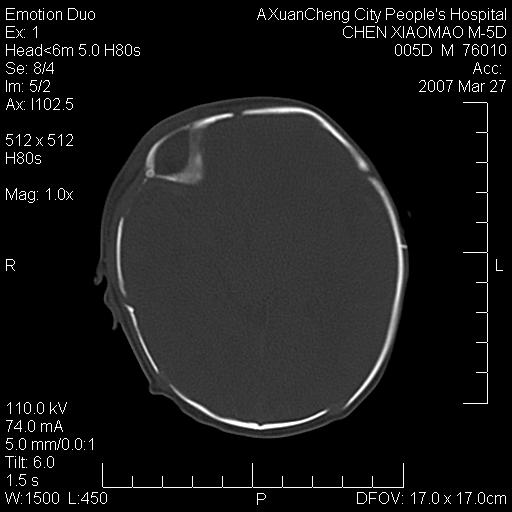

大家看看可有出血?另外枕骨中央是骨缝还是骨折

颅内未见明显异常。枕骨鳞部应为假缝(颅外软组织无肿胀),有外伤吗?

左颞枕部有出血,枕骨有骨折

枕骨骨折可以下,应该比较明显,颅内还是正常的,不放心的话,短期随访。

未见明显异常,,那是横窦影,“缝”是后囟